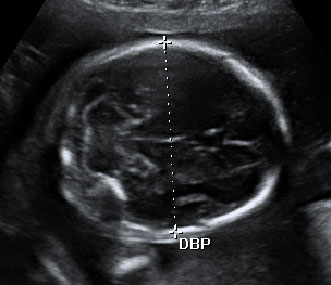

La imagen ecográfica en dos dimensiones es básica para obtener la imagen en 3D en tiempo casi real.